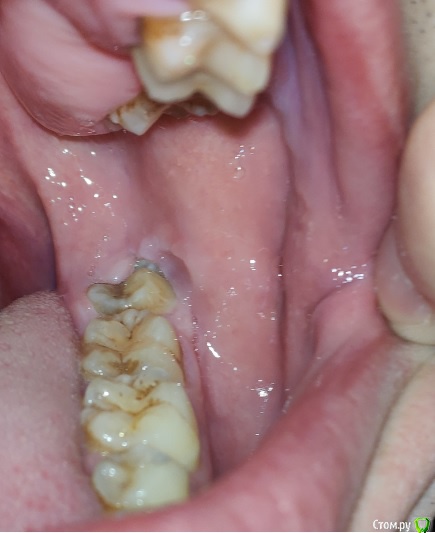

posman Опубликовано 8 октября, 2018 Поделиться Опубликовано 8 октября, 2018 (изменено) Здравствуйте! Просьба проконсультировать касаемо возможной "природы" образований на фото.Наросты выявлены около 10 лет назад при очередном осмотре у ЛОР-врача.Симметричны с двух сторон языка, на левой стороне более выражены. Динамика роста отсутствует, в последние 2 месяца отмечена некоторая болезненностьс левой стороны у корня языка, отдающая в область нижнего 8го зуба и небной дужки(ноющий дискомфорт в т.ч. при употреблении пищи). В ночное время боль отсутствует. За последнюю неделю слева появилось небольшое желтое "включение", м.б. нагноение (видно на фото в динамике). В течении двух месяцев посетил трех лоров, чл-хирурга и двух специалистов по слизистым,выполнено МРТ мягких тканей шеи (без патологий).Фарингоскопия также патологий не выявила, ЧЛХ связал болезненность с 8м зубом, который до конца не прорезалсяи имеет десневой карман. Один специалист по слизистым поставил глоссит, второй коллега указал на вероятную глоссалгию.Касаемо "наростов", мнение стоматологов - физиология и сосочки языка. ЛОРы - лимфоидная ткань язычной миндалины.За время "истории" прошёл противогрибковую терапию (флюкостат), антибиотики не употреблял. бак-посев не выявил патогенной микрофлоры, ОАК месячной давности в пределах нормы. По сути, интересует три момента:1. Природа наростов. Понимаю, что точно может показать только гистология, но хотя бы визуально. 2. Возможная связь дискомфорта с зубом мудрости, карманом или др.неврологической причиной. 3. "Гнойник" на наросте, что делать, как лечить. Фото языка и 8ки, а также снимок ОПТГ прилагаю. Буду признателен за комментарии. Изменено 8 октября, 2018 пользователем posman Ссылка на комментарий

posman Опубликовано 9 октября, 2018 Автор Поделиться Опубликовано 9 октября, 2018 и... забить 10 лет так и делал, пока не возник дискомфорт в этой области. Еще вопрос: что можно сказать по 8ке исходя из снимка ОПТГ? Мнение двух стоматологов разошлись: 1. зуб без кариеса и пока удалять не стоит. Предлагают устранить карман сбоку. Стоит это делать?2. 8ке не хватает места и она давит на рядом стоящий 7й зуб, что может привести к кариесу и потере последнего, т.е. необходимо удаление зуба мудрости. Также уточните пожалуйста, пока не попаду к врачу, стоит ли чем-то обрабатывать воспаление (желтый гнойник сбоку).Появился за пару дней. м.б. пополоскать содой? или по фото совсем не понятно что это? Ссылка на комментарий